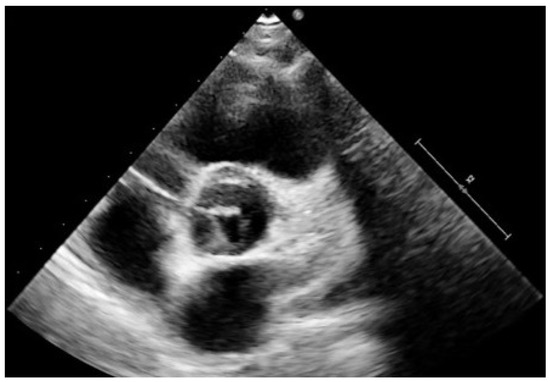

4. Clinical Presentation in Different Paediatric Ages and Natural History

5. Diagnostic Imaging